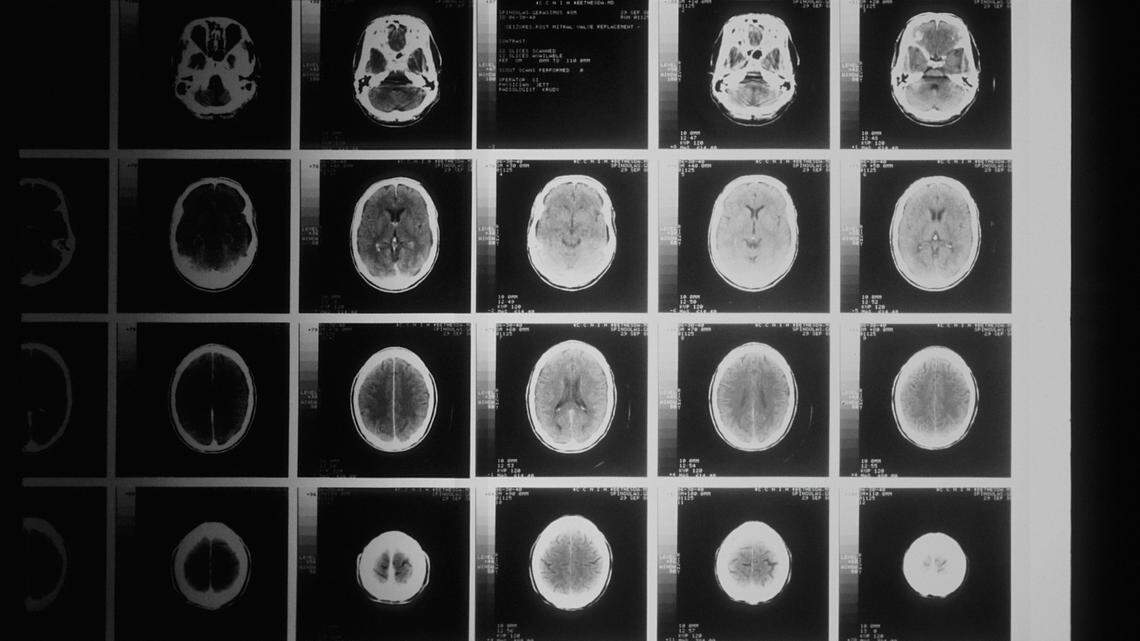

In 2023, the then 49-year-old went to her physician with painful headaches, blurring vision, pain and swelling of her eyes and difficulty communicating, the lawsuit says. Her doctor ordered MRI and CT scans, leading to the discovery of three “densely calcified meningiomas.”